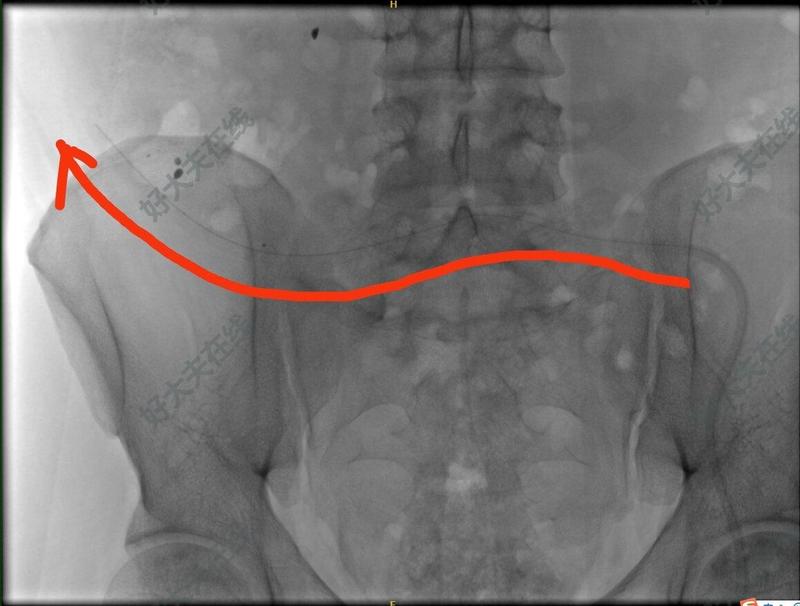

腹膜透析腹透管漂管

治疗前丹东来患者杜xx,腹膜透析1年余。腹透超滤量为负400至750ml每天,伴浮肿,高血压,气短。术前x光提示腹透管漂管。治疗中中国医科大学附属第一医院肾内科及腹透中心朱新旺医生,采用不开刀,无创式,介入复位技术,将腹透管复位。治疗后治疗后7天腹透管复位成功,超滤正常,浮肿缓解。

治疗前肥胖患者,腹膜透析置管术后2个月。超滤困难,浮肿加重。查盆腔X光提示腹透管漂管。治疗中中国医科大学附属第一医院肾内科腹透中心朱新旺医生,不开刀不手术,利用导丝无创复位漂管的腹透管。治疗后治疗后7天患者恢复正常腹透。超滤量500到700ml每天,浮肿消退。